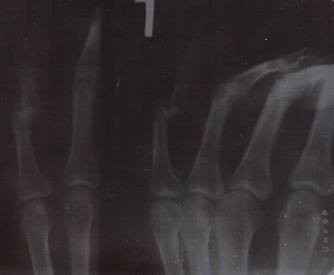

Как и обещал, выкладываю ренген, вчерашний!

Вкладення

Rengen11.jpg

Rengen11.jpg (60.98Кіб)Переглянуто 5563 разів